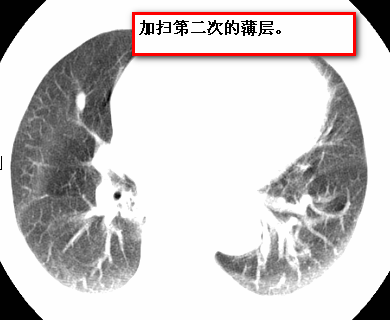

标题: CT26680:肺部右下肺静脉干结节的界定 [打印本页]

标题: CT26680:肺部右下肺静脉干结节的界定

经追查说有支扩咯血病史,但不确定

考虑1、周围型肺癌,2肺静脉畸形,前者可能大,建议增强检查。

不排除右肺下叶周围型肺癌可能。